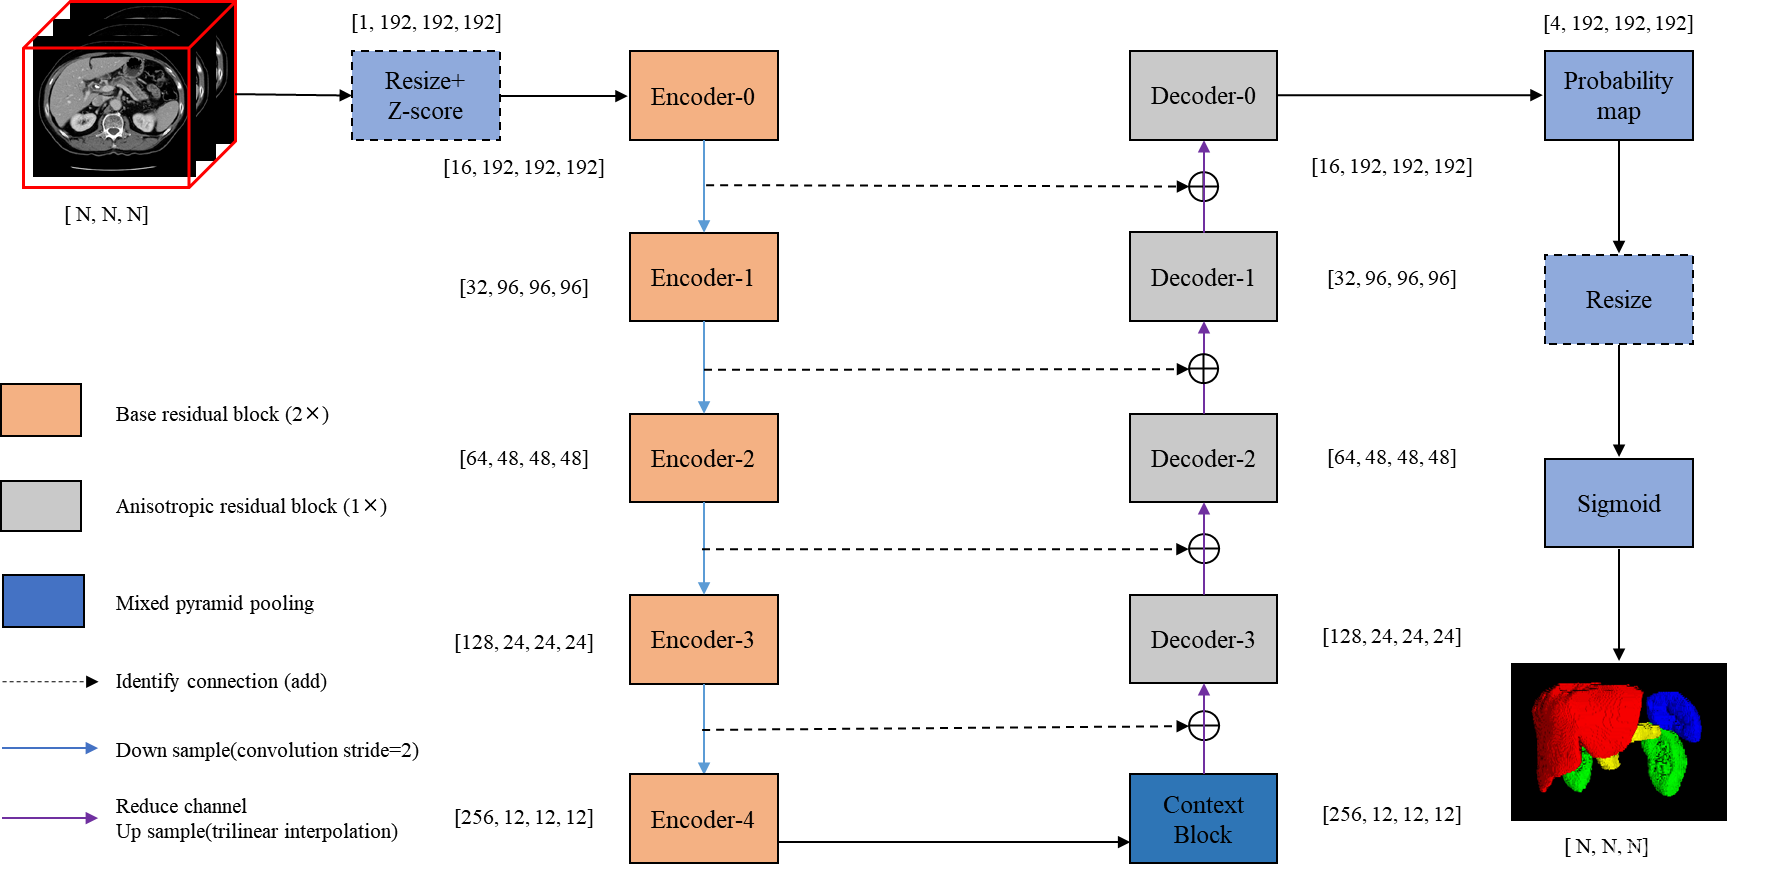

Network

EfficientSegNet网络,该网络由basic encoder、slim decoder和efficient context模块组成。在decoder模块中引入anisotropic卷积,提升了网络计算效率;设计mixed pyramid pooling的context模块,融入strip pooling结构,提升了anisotropic和long-range上下文特征的表示能力。相较于self-attention和non-local模块,strip pool具有更低的显存占用和矩阵运算量。算法实现上,采用混合精度、分布式训练技术来缩短训练过程时间,提升显存利用效率。在推理过程中,采用CUDA加速图像预处理和后处理,FP16量化推理提升模型推理效率。

Encoder/Decoder

如图所示,编码器模块由两个残差卷积块组成,解码器模块由一个残差卷积块组成。在解码器模块中,我们将一个核大小为3×3×3的标准3D卷积分离为3×3×1片内卷积和1×1×3片间卷积。残差卷积块的实现如下:convent -instnorm-ReLU- convent -instnorm-ReLU(残差的加入发生在最后一个ReLU激活之前)。

Context block

我们采用基于3D-based mixed pyramid pooling (3D的混合金字塔池化)方法提取背景特征,该方法由标准空间池化和各向异性条带池化两部分组成。标准空间池使用两个平均池,大小分别为2×2×2和4×4×4。anisotropic strip pooling具有三个不同方向的感受域:1×N×N, N×1×N, N×N×1,其中N为上一个编码器模块中feature map的大小。

粗模型初始特征图个数为8,细模型初始特征图个数为16。我们通过添加而不是连接来聚合低级的水平特性,因为前者消耗的GPU内存更少。此外,对于192×192×192输入大小,模型参数的数量是9 MB,失败的数量是333 GB。

本文基于UNet,对Encoder、Decoder、Context block进行如下优化:

- 对比Basic Convolution、Bottleck Convolution、Depthwise Separable Convolution、Anisotropic Convolution,Encoder最优选择为Basic Convolution,Decoder最优选择为Anisotropic Convolution。相对于Basic Convolution,其他卷积方式具有更低的运算复杂度,但是分割指标存在一定程度的下降。Decoder采用更低复杂度的Convolution block,对于分割指标影响较小。

- 对比SPP block(https://arxiv.org/abs/1612.01105)、StripPooling block(https://arxiv.org/abs/2003.13328)、AnisotropicAvgPooling block,AnisotropicAvgPooling block具有更优的上下文特征表示能力

- 不同尺度特征的融合方式,本文将upsample+concate+convolution的融合方式,修改为down channel+upsample+add+convolution,后者计算复杂度更低

- 采用非对称的UNet结构,Encoder采用4层卷积block(包含2个residual block),Decoder采用2层卷积block(包含1个residual block)